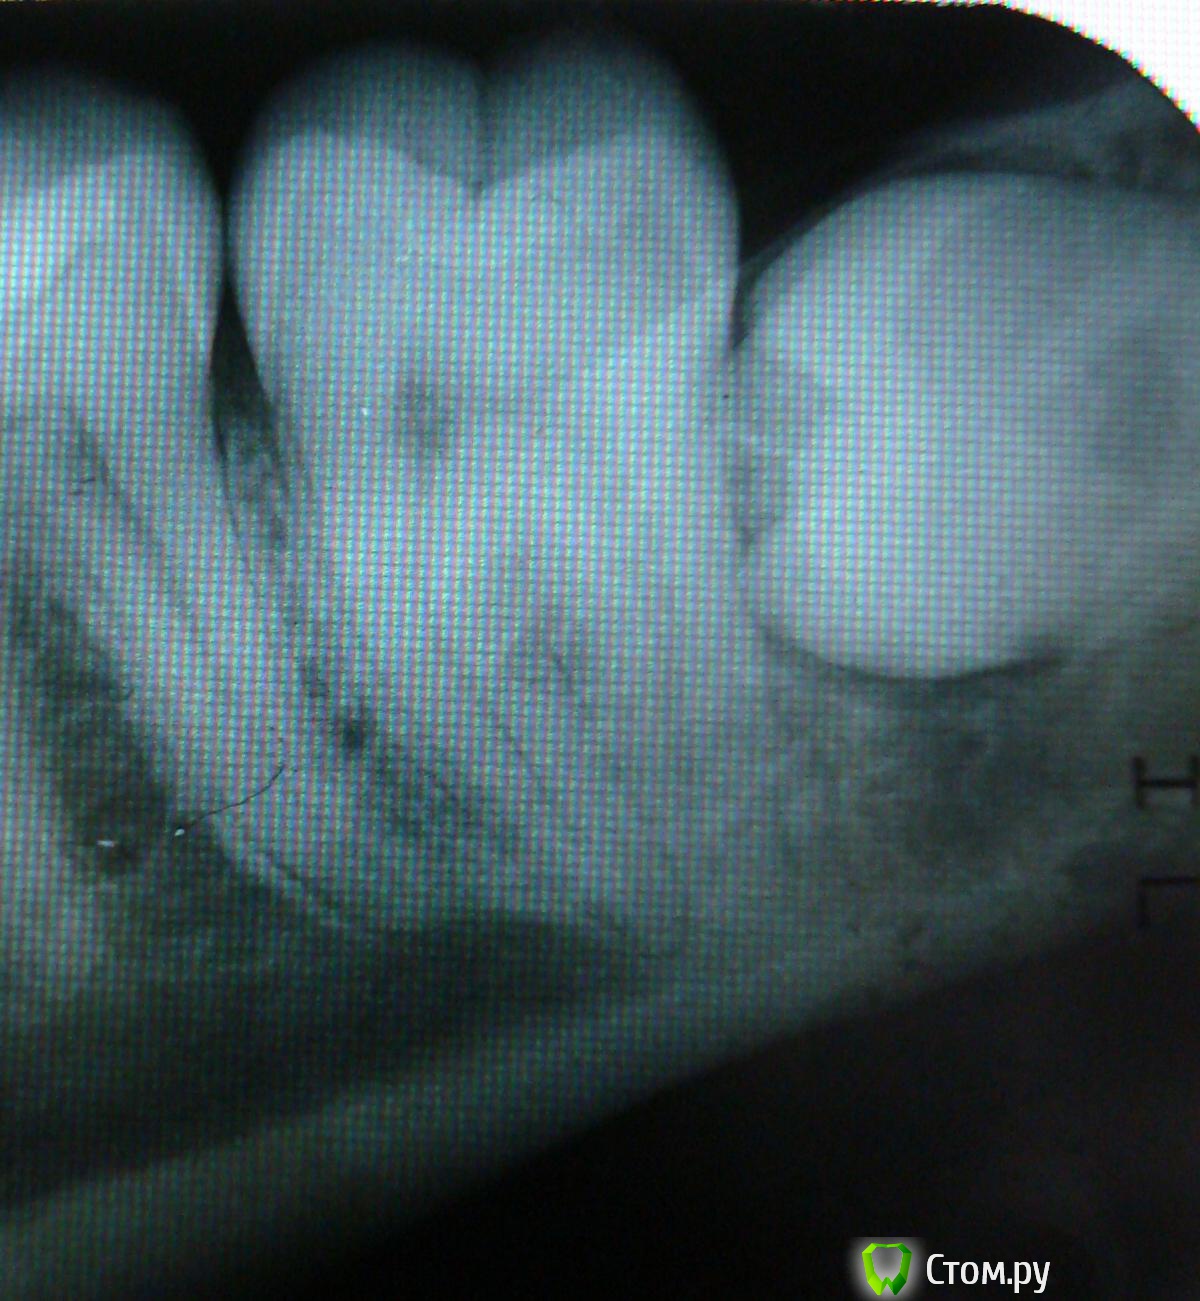

Irina B. Опубликовано 15 августа, 2014 Поделиться Опубликовано 15 августа, 2014 Здравствуйте! Снизу слева между 7 и 8 зубами потемнение на снимке. Посмотрите, пожалуйста, это кариес или тень от 8 зуба? 8-й зуб непрорезавшийся совсем, мне 26 лет. Ссылка на комментарий

Бардо Опубликовано 15 августа, 2014 Поделиться Опубликовано 15 августа, 2014 8 нужно удалять. Кариеса явного по снимку я не вижу Ссылка на комментарий

red_butler Опубликовано 15 августа, 2014 Поделиться Опубликовано 15 августа, 2014 Удалить восьмерку и посмотреть глазами 3 Ссылка на комментарий

Irina B. Опубликовано 16 августа, 2014 Автор Поделиться Опубликовано 16 августа, 2014 Спасибо. А на верхней поверхности в 7 зубе кариес есть или нет, судя по снимку? Ссылка на комментарий

red_butler Опубликовано 18 августа, 2014 Поделиться Опубликовано 18 августа, 2014 И снимок не очень, и не всегда начальный кариес на снимке виден. Нужен очный осмотр Ссылка на комментарий